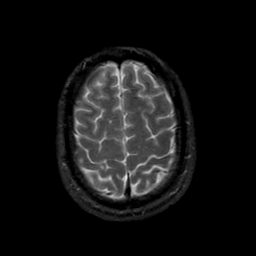

MR Study #21, November 3, 1991 -- Slice #41

[Home][Help][Clinical][Tour 1][Tour 2] Slice 41